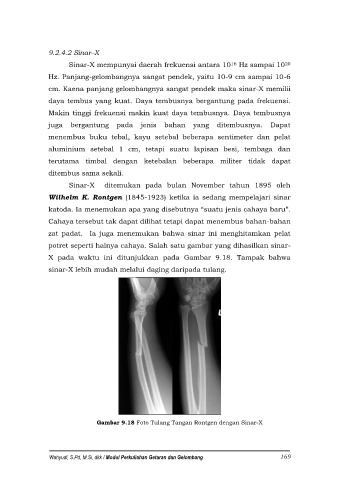

potret seperti halnya cahaya. Salah satu gambar yang dihasilkan sinar-

X pada waktu ini ditunjukkan pada Gambar 9.18. Tampak bahwa

sinar-X lebih mudah melalui daging daripada tulang.

Gambar 9.18 Foto Tulang Tangan Rontgen dengan Sinar-X